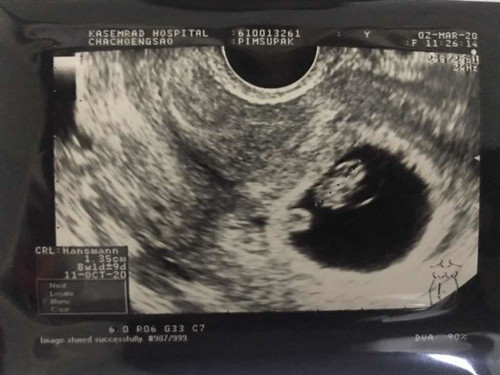

8 สัปดาห์ความยาว 1.35cm ถือว่าปกติไหมคะ

8w